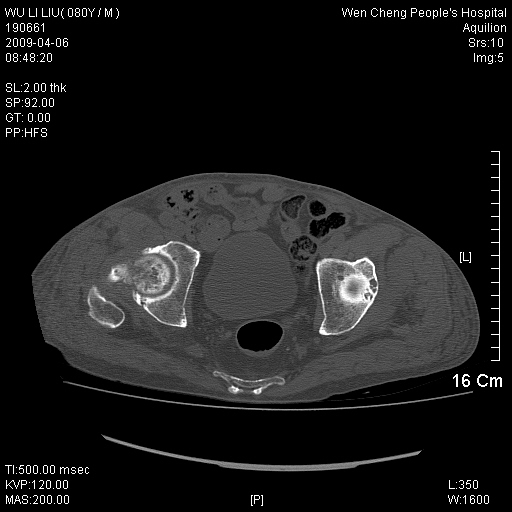

以下是引用zjzjr在2009-4-7 12:13:00的发言:[br]支持多发性转移瘤,右股骨颈骨折,腰椎亦有压缩性骨折.肝内胆管结石伴胆内外胆管扩张,左肾结石.

以下是引用liaoqiang在2009-4-7 8:44:00的发言:[br]考虑多发性骨髓瘤伴肝肺转移、肝内胆管结石、左肾结石、右股骨颈骨折。

以下是引用余辉在2009-4-7 8:52:00的发言:[br]椎骨及骨盆骨质疏松,骨破坏主要累及椎体,各骨破坏较广泛,各病灶边缘均较清晰锐利,血沉增快,白细胞增高.支持考虑多发骨髓瘤,建议查本尿周氏蛋白.[br]胆内胆管及左肾结石[br]右股骨颈骨折,考虑病理性